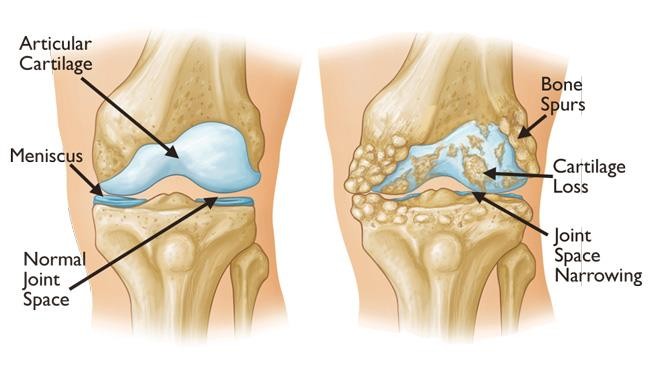

- اسکن تصویربرداری از گوش میانی شما برای ارزیابی آسیب رکابی

درمان اتواسکلروز به میزان کم شنوایی بستگی دارد. در مواردی که کم شنوایی خفیف است، گوش و حلق و بینی ممکن است یک رویکرد انتظار و دید همراه با آزمایشات شنوایی منظم را توصیه کند. اگر کم شنوایی شما خفیف تر باشد سمعک می تواند گزینه دیگری باشد. همچنین اگر کم شنوایی پیشرفتهتری از اتواسکلروز دارید، کاشت حلزون نیز در نظر گرفته شود. کم شنوایی شدید نیز ممکن است با جراحی به نام استاپدکتومی درمان شود که شامل برداشتن رکاب ها و جایگزینی آنها با یک وسیله مصنوعی برای کمک به بهبود شنوایی شما است. تصور می شود که جراحی در 90٪ موارد به بهبود اتواسکلروز کمک می کند.